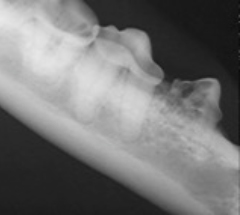

«Periodontitt» er navn på en kronisk infeksjon og betennelse i tannkjøtt og kjevebein. Mens denne betennelsen pågår er munnen veldig ofte smertefull, illeluktende og tannkjøttet kan lett blø. Hvis ikke sykdommen blir behandlet grundig vil tennene, en etter en, løsne fra kjeven og falle ut eller må trekkes. I verstefall kan periodontitten resultere i en brukket underkjeve eller en perforasjon/fisteldannelse i beinsubstansen mellom ganen og nesen.

Behandling går ut på dyp og grundig tann og tannkjøttrens for å bremse utviklingen av sykdommen. Det tas tannrøntgenbilder. Tenner som ikke kan reddes blir trukket. Tann og tannkjøttstatus kartlegges og eieren får veiledning om forebyggende hjemmepleie og om oppfølgingstimer til regelmessig tannkjøttrens. Hvor ofte dyret må ha behandling for denne kroniske sykdommen er veldig individuelt.

Tannresorpsjoner

Denne sykdommen er et veldig vanlig tannproblem hos katt og i mindre grad hos hund. Tannen begynner spontant å gå i oppløsning, «resorpsjon». Når resorpsjonen er på krona er tannen veldig vond. Katter med denne sykdom vil ofte endre atferden. For eksempel kan de sikle mer og spise mindre. Tannresorpsjon kan utvikle seg på en eller flere tenner samtidig. Tannrøntgenbilder tas. Basert på nivå av resorpsjon vil tannen ble operert ut eller amputert kirurgisk. Denne sykdommer utvikler seg på flere tenner etterhvert, derfor er det viktig at dyret følges med regelmessig munnhuleundersøkelse, tannrens og tannrøntgenbilder. Informasjon og rapport til eieren.